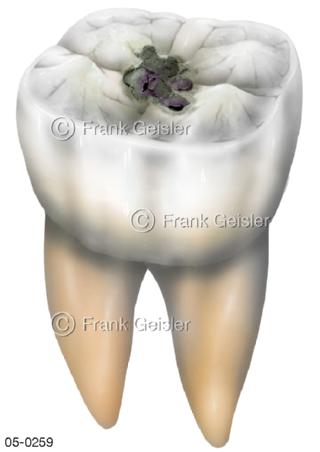

Bildergalerie Skelettsystem

Bilder zum Skelettsystem zeigen die Stützstruktur des menschlichen Körpers, die Knochen, eine besonders harte Form des Bindegewebes und Stützgewebes, welche das menschliche Skelett bildet, die Knochen des Stammes, der Extremitäten sowie der Gelenke